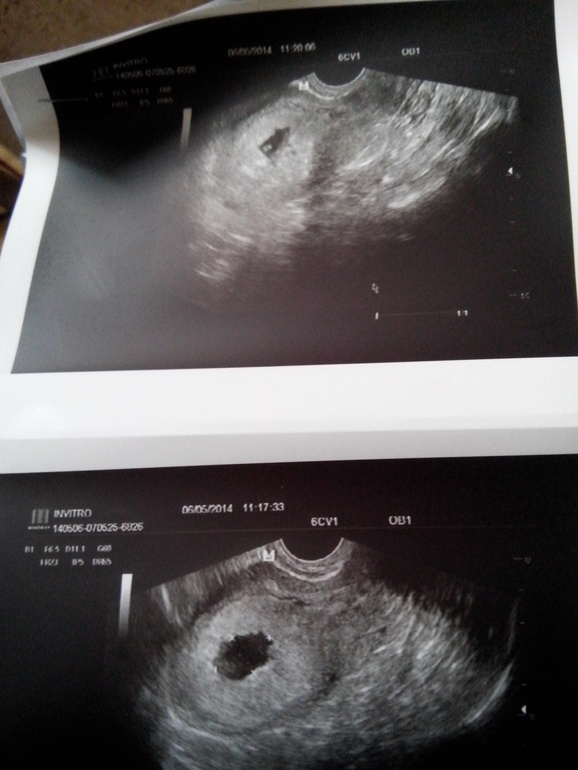

На первом снимке есть что-то в яице, не спешите с чисткой!!!!у меня была 3 недели задержки и я смотрела на узи там ничего не было только хгч показал маленькие результаты,которые начали расти!)и оказалась что это была поздняя овулька и нам тогда только 2 недельки было от зачатия,все потому что цикл не постоянный))и врач потом сказала что это дисфункция яичников,а сейчас все хорошо и мы развиваемся))))да и тогда когда искала причину почему не видят эмбриона поехала в боткинскую-там сделали узи и сказали что это вообще замершая,но нам дали снимочек,я вышла и моя мама сказала:что вот посмотри в яйце точечка,это ваш малыш и не плачь!!!)надо верить в лучшее,вы его так ждали!!)я поверила и через 3 недели наше сердечко за стучало))))все будет хорошо надо только верить!!!)

спасибо за поддержку) это первый снимок, а вот на последнем, т.е на пред последнем та тоже что то есть, но врач сказала что не понимае что, скорее всего замершая беременность(

Хгч более чем! Конечно, уже дб эмбрион. Сходите к другому узисту. А предыдущие хгч? По-моему все там видно

Александра

Плодное яйцо видно,но эмбриона я там не вижу.Я не врач,конечно.Но деформированное плодное яйцо не очень хорошо.А ХГЧ очень высокий.Вы к врачу ходили?К гинекологу?

2D мама

Подождите!!! Не делайте ничего! У меня двойня, один из эмбрионов визуализмровался только на 7-8 неделе!!!! А так было тоже плодное яйцо пустое.